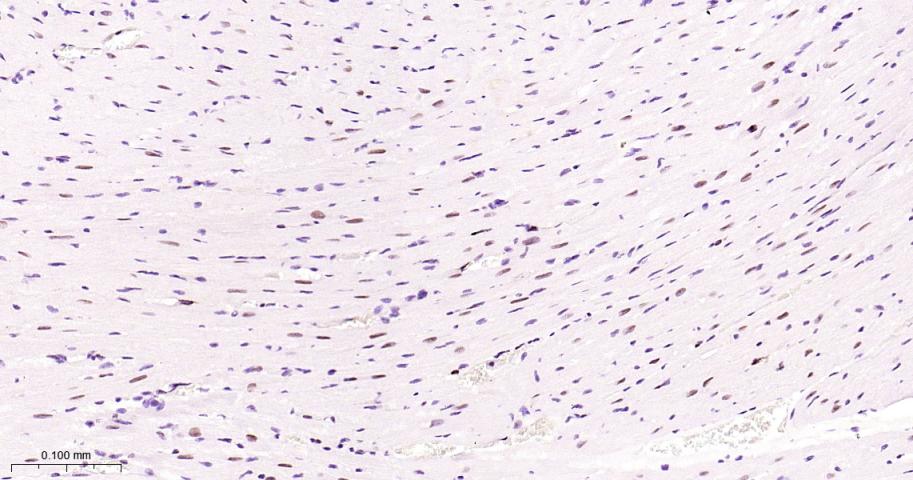

Paraformaldehyde-fixed, paraffin embedded Mouse Heart; Antigen retrieval by boiling in sodium citrate buffer (pH6.0) for 15 min; Antibody incubation with PCNA Monoclonal Antibody, Unconjugated(bsm-33035R) at 1:200 overnight at 4°C, followed by conjugation to the bs-0295G-HRP and DAB (C-0010) staining.